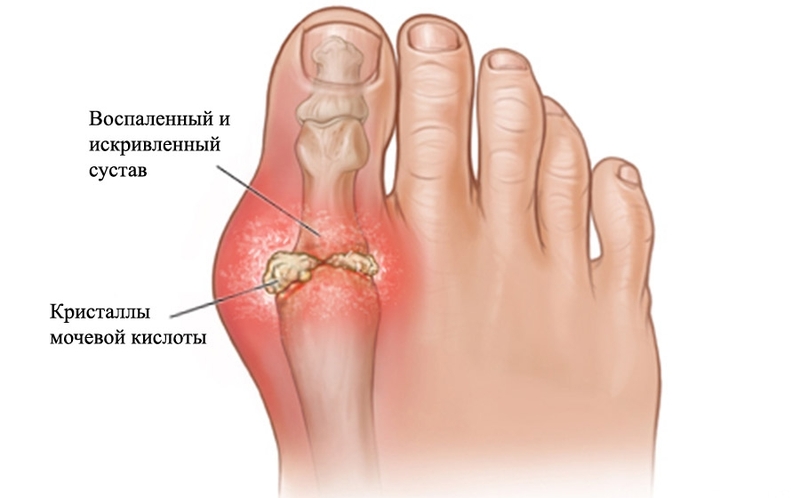

Подагра — ревматическое заболевание, причиной которого становятся тофусы, или кристаллы мочевой кислоты, постепенно накапливающиеся в полости сустава. Клинически патология проявляется рецидивами артрита. Человек страдает от мучительных болей в суставах, их отечности и скованности движений. Постепенно в патологический процесс вовлекаются почки — развивается мочекаменная болезнь. При тяжелом течении подагры у больных диагностируется почечная недостаточность. Нарушается мочевыделение, усиливаются отеки из-за задержки жидкости в организме.

МК в небольшой концентрации требуется нашему организму, поскольку защищает его от раннего старения и раковых заболеваний. Если человек не болеет, избыток МК выводится почками. Когда обмен пуринов нарушается, МК начинает накапливаться в большом количестве. Ее соли кристаллизуются и откладываются в суставных сочленениях, почках и других тканях, провоцируя атаку подагры.